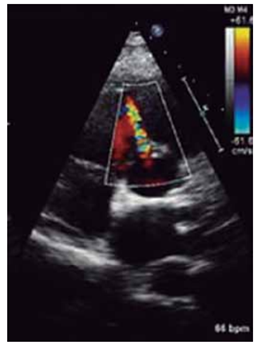

A imagem apontada pela seta indica:

(Arquivo pessoal; imagem utilizada com autorização)